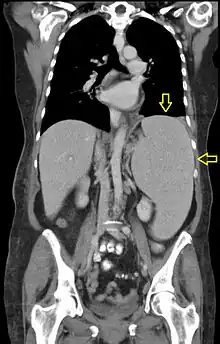

CT scan in a patient with chronic lymphocytic leukemia, showing splenomegaly. Yellow arrows point at the spleen.

Abdominal CT is the most accurate. The spleen needs to be 2–3 times larger than normal to be palpable below the costal margin in physical examination.